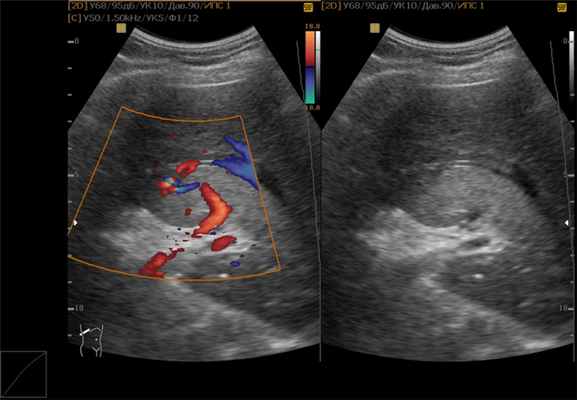

- ультразвуковое исследование. Гемангиома печени на УЗИ зачастую заметна в паренхиме печени в виде округлого образования с неоднородным содержимым и четкими контурами;

- Ультразвуковое исследование. Метод визуализации органов и анатомических структур. В его основе лежит использование высокочастотных звуковых волн, которые отражаются от органов, с формированием изображения.

- контрастно-улучшенный ультразвук – высокочастотные звуковые волны проходят через ткани тела, а эхо-сигналы записываются и преобразуются в видео или фотографии;